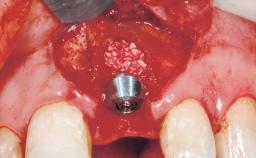

A 29-year-old female patient presented for treatment to replace the upper left central incisor tooth with an implant- supported restoration. The tooth had been intermittently symptomatic for the previous 12 months. The tooth had originally suffered trauma about 15 years previously. Several endodontic treatments had been performed, including an apicectomy procedure to retain the tooth. The patient was healthy and a non-smoker. She had reasonable expectations in regard to esthetic outcomes and the risk of marginal tissue recession following treatment. At medium smile, the gingival margins of the upper teeth were visible, with a display of 3 to 4 mm of the gingival margins. Gingival recession of tooth 21 and a discrepancy in the gingival levels between teeth 11 and 21 was observable during normal speech and smile.

Placement Protocol | Immediate implant placement |

Socket Morphology | Single-root socket |